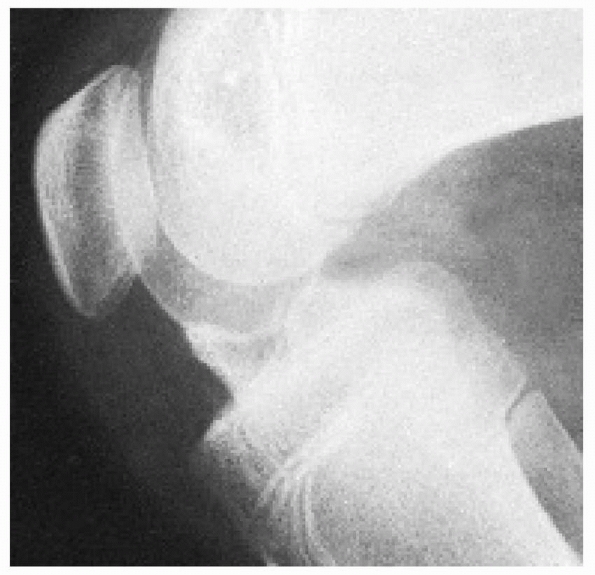

For symptomatic patients, this can be corrected by excision of the

manumitted fragment and anatomic reinsertion of the ACL. Alternatively,

excision of the fragment and ACL reconstruction can be considered in

![]() |

FIGURE 24-12 Lateral radiograph of a malunited displaced fracture of the intercondylar eminence of the tibia with an extension block.